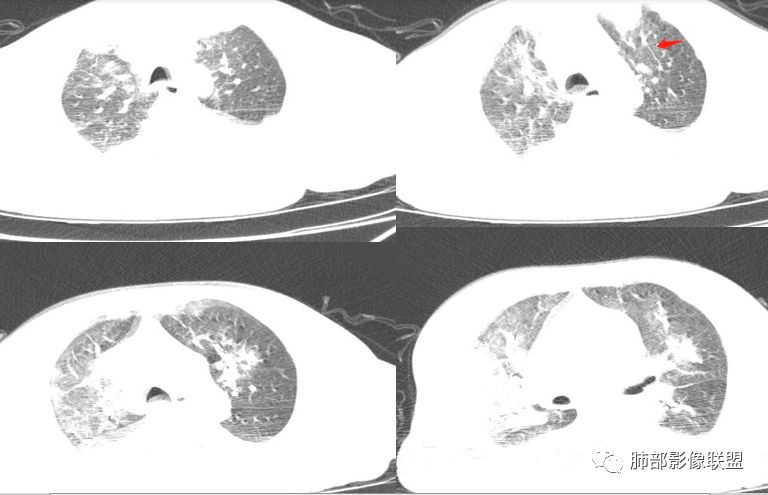

两肺渗出,胸膜腔积液,左室显著增大,首先考虑肺水肿,建议治疗后复查。左肺上叶舌段病灶似有支气管截断征。

急性起病,左心大,双侧胸腔积液,双肺实变,肺水肿肯定有,但右肺容积缩小,估计得二元论

心脏增大,以左心室增大为主,胸腔积液,以右侧为甚,小叶间隔增厚——左心衰竭?肺主动脉增宽——肺动脉高压?左肺上叶前段以及肺门处见多个斑片状高密度影——感染(类型:细菌?病毒?),不像肺水肿分布改变

湿啰音明显,心衰应该有的,但是不是还合并有病毒感染,因为病灶外带也不少

中轴间质增厚,沿支气管走行实变影,部分边缘显示膨隆,小叶间隔增厚不确切,左肺舌段和下叶前内基底段支气管狭窄,好像远端未见显示,淋巴增生性病变?

起病急,双肺实变以内中带为著,左心大,小叶间隔光滑增厚,心衰肺水肿成立,病人年纪大,不知有否基础病,肺内改变形态多样化,有实变有结节,考虑二元,肺水肿,努卡?

两肺大片状实变影,中内带为主,边缘稍模糊

周围大片GGO

小叶间隔增厚

这个不是特别像直接流感造成的病毒性肺炎,分布不是很符合或者不是最典型的。比较像是流感激发的暴发性心肌炎,引起的一个爆发性心衰的继发性的变化。我个人看法是这样的,这个病例可能没有最终的结果,分析思路可能是这样。因为前面确实有感冒病史,但有没有体温异常,有没有那个流感中毒不知道,5天后出现的症状,显示的是肺水肿,但他是区别病毒性肺炎,一般的早期状态的,所以说应该来讲还是类似于爆发性心衰。就是流感-并发症-暴发性心肌炎-心衰-肺水肿。

熊老师是考虑病毒继发的心衰,从病史看,还是支持;影像上:肺水肿是明确的;如果病毒性肺炎影像上重叠